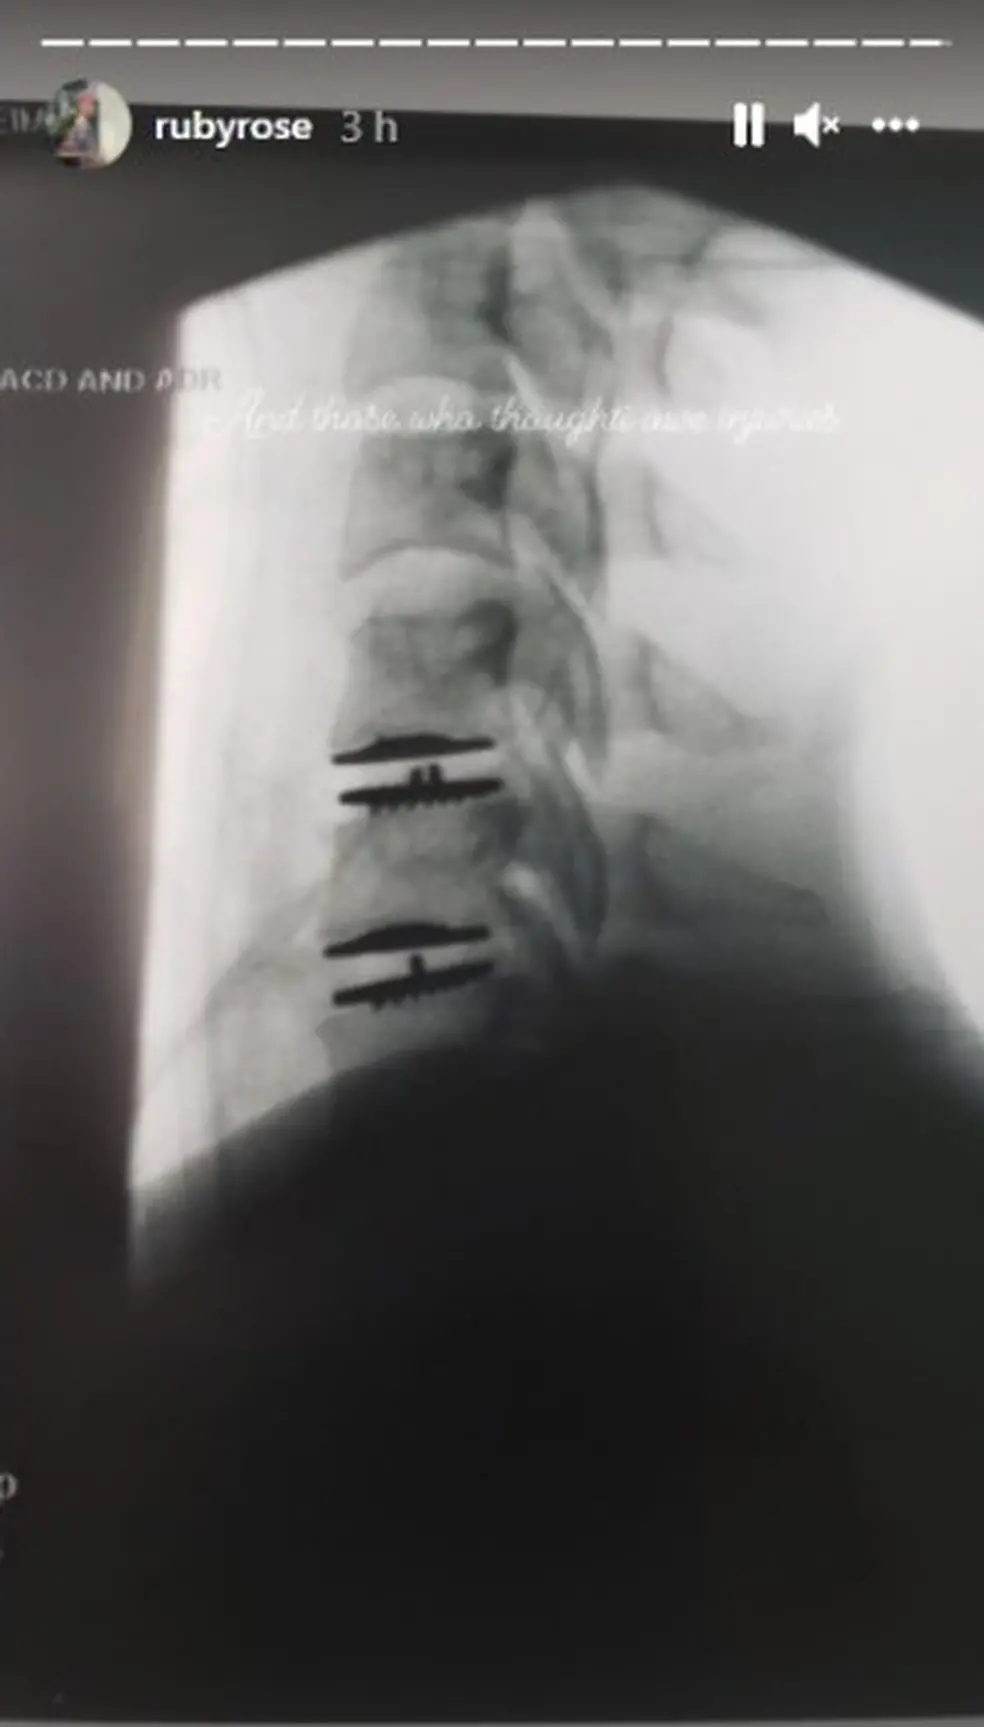

Fraturas mostradas em exames

Legenda: Ruby Rose exibe fratura na coluna causada por gravações de Batwoman

Foto: Reprodução Instagram

Entre as situações, a atriz diz ter sofrido "cortes tão perto do rosto que poderia ter ficado cega" durante a gravação de uma cena. Rose alega também ter sido forçada por produtores da série a voltar ao set apenas 10 dias após ter passado por uma cirurgia de emergência na coluna, após sofrer fraturas que poderiam tê-la deixado paraplégica.